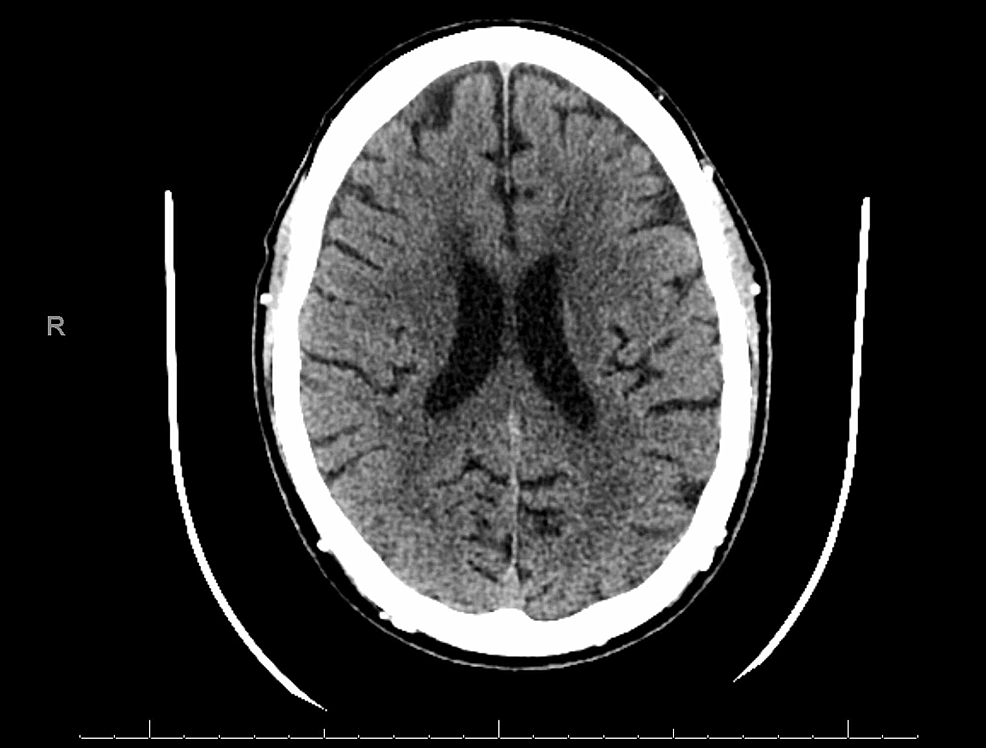

Herpes simplex virus causes genital herpes, labial herpes, brain inflammation due to herpetic infection herpetic encephalitis, herpes simplex keratitis, shingles, herpes zoster, and chicken pox. |